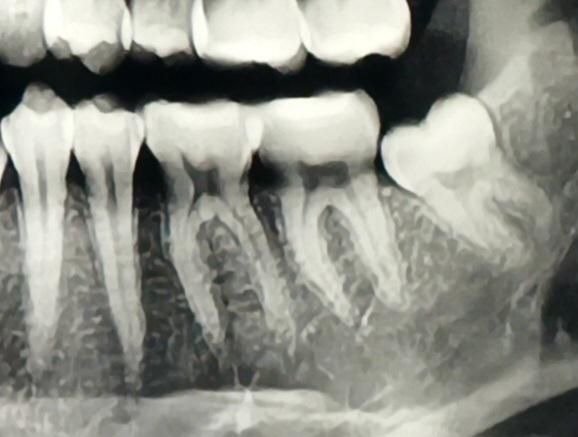

사랑니 발치 후 어금니 쪽 통증 욱신거림

사랑니를 발치한지 일주일짼데 어금니 쪽이 욱신거리네요. 통증도 있고 음식 씹을때도 가끔이지만 아파요. 이가 맞닿을때 느낌이 이상하기도 합니다.

매복 사랑니에 신경관에 가깝다곤 했는데 원래 어금니도 같이 아픈건지 모르겠네요.

엑스레이도 찍었고 검진받을땐 어금니에 대해서는 별 말씀 없으셨습니다. 충치일 가능성도 있을까요?

• 1번 째 사진